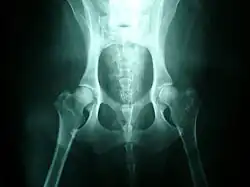

Hip dysplasia is diagnosed with radiographs of the pelvis. It is also common to X-ray the spine and legs, as well as the hips, since soft tissues can be affected by the extra strain of a dysplastic hip, or there may be other undetected factors such as neurological issues (e.g. nerve damage) involved.